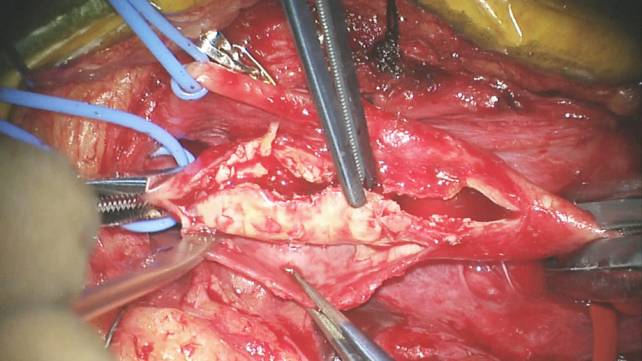

下面的术中照片用来举例说明右侧经内动脉内膜剥脱术的手术步骤:

图21d. 移除斑块后小心检查颈内动脉管腔。小片内膜瓣最好在缝合血管时钉合在血管壁上。

图21e. 小心检查管腔,清除所有明显的内膜瓣。

图21f. 颈内动脉管腔狭小提示需要使用补片成形术。在缝针穿过补片和血管壁后折返防止缝合后漏血。

图21g. 血管壁的大边距缝合将血管壁拉入缝线内能预防不规则的外缘碎片凸向管腔。